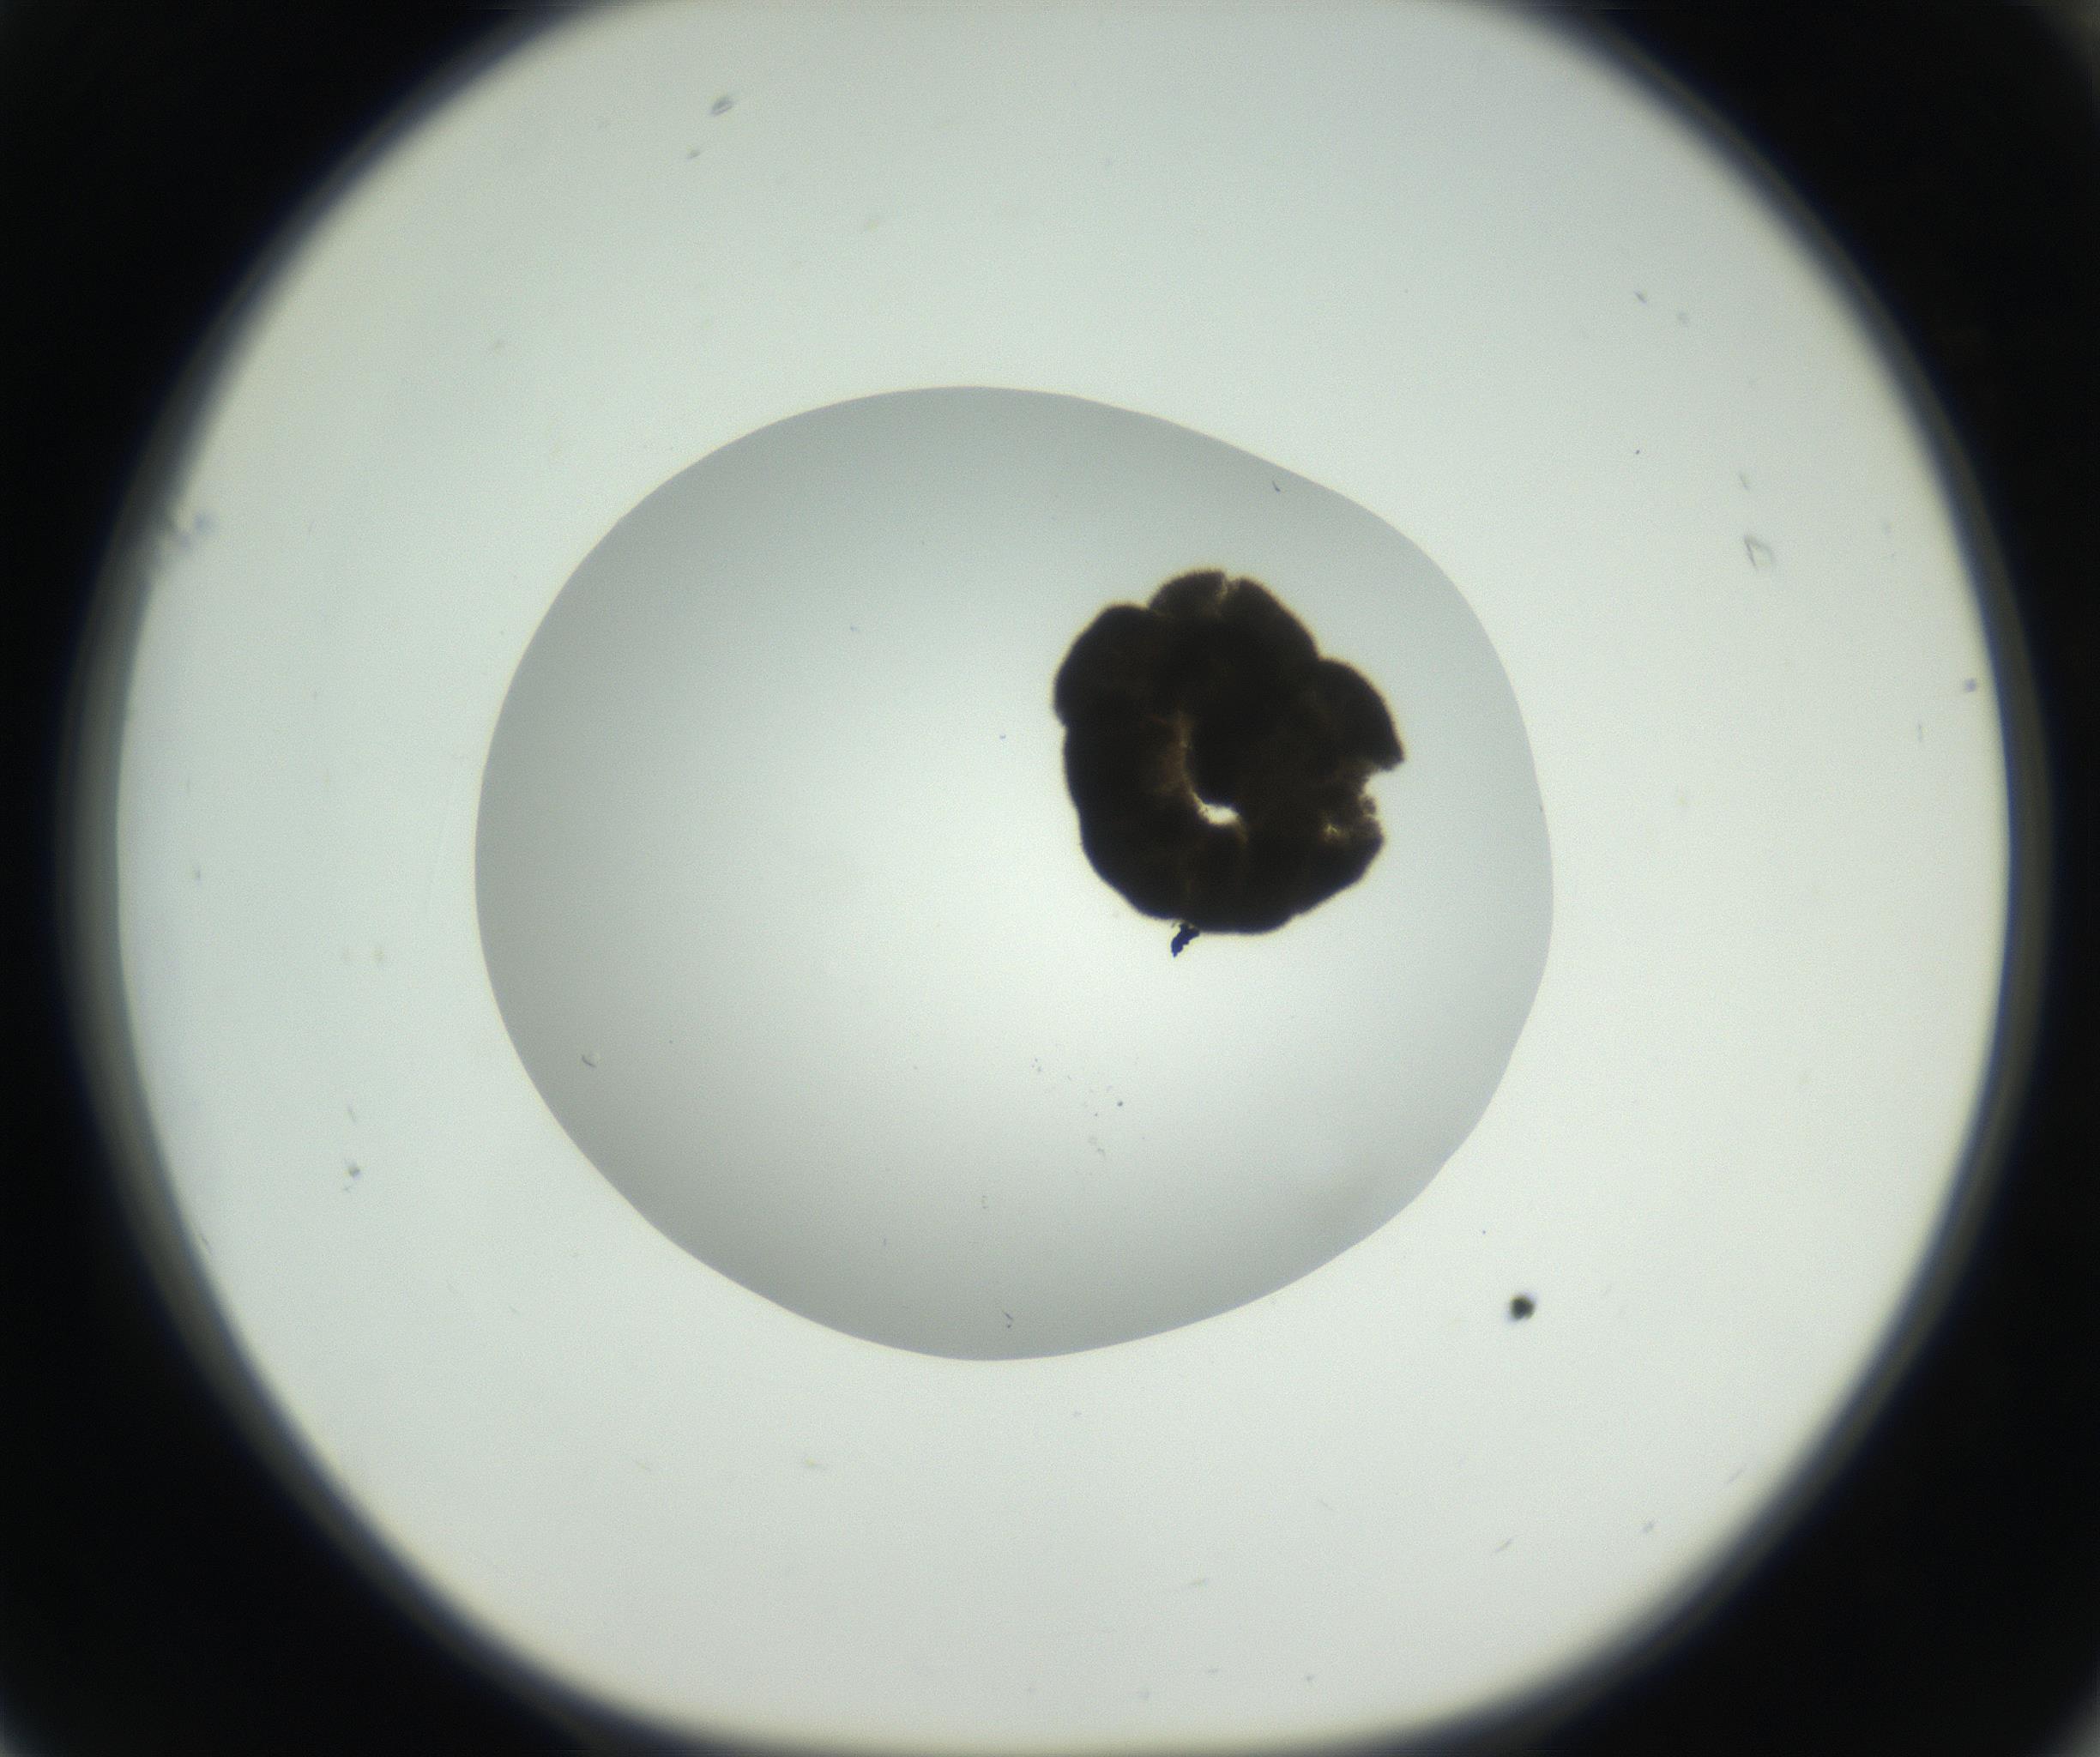

RI01_03_000_0212_Proj1_Clon1_MC_0000MC102666_004_160828_01_06_01_00_99_002_001_RAI.jpg